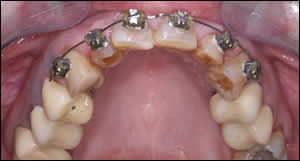

Fig 10: A coil spring was used to position tooth # 7 equidistant between tooth #6 and 8. An elastic chain was utilized on the lower arch to close the space that was created by uprighting tooth #24 and 26. Note tooth #25 is missing.